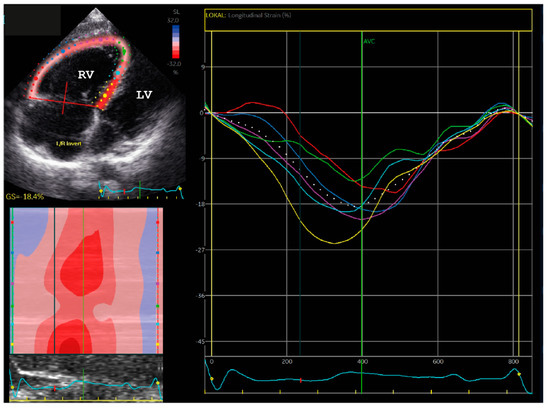

2.1. Clinical Description of the Patients

2.1.1. Family A

2.1.2. Family B